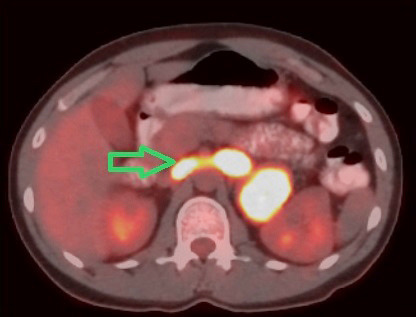

Pheochromocytomas are potentially malignant and may manifest with vascular thrombi. We present the treatment of a patient with pheochromocytoma and tumor thrombosis of the renal vein and inferior vena cava. A thirty-eight-year-old male patient was admitted complaining of abdominal pain and headache. High levels of urinary catecholamine were detected. Magnetic resonance imaging revealed left pheochromocytoma with thrombosis of the inferior vena cava and the left renal vein. A left adrenalectomy and a thrombectomy with cavotomy were performed. The pathology results reported a 9.5 cm malignant pheochromocytoma. The patient's symptoms dissipated after the operation and there were no signs of recurrence at the two-month follow-up. Preoperative radiological diagnostic examinations are valuable in the planning of pheochromocytoma surgery. We believe that adrenalectomy and thrombectomy can be performed on pheochromocytoma patients with vascular thrombi with low morbidity.